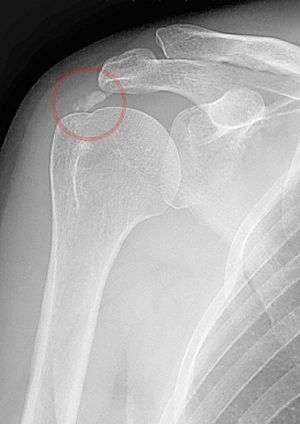

A plain X ray of the shoulder showing calcific tendinitis | |

Calcific tendinitis is a form of tendinitis, a disorder characterized by deposits of hydroxyapatite (a crystalline calcium phosphate) in any tendon of the body, but most commonly in the tendons of the rotator cuff (shoulder), causing pain and inflammation. The condition is related to and may cause adhesive capsulitis ("frozen shoulder").

The calcific deposits are visible on X-ray as discrete lumps or cloudy areas. The deposits look cloudy on X-ray if they are in the process of reabsorption, and this is also when they cause the most pain. The deposits are crystalline when in their resting phase and like toothpaste in the reabsorptive phase. However, poor correlation exists between the appearance of a calcific deposit on plain X-rays and its consistency on needling. Ultrasound is also useful to depict calcific deposits and closely correlates with the stage of disease.[1]